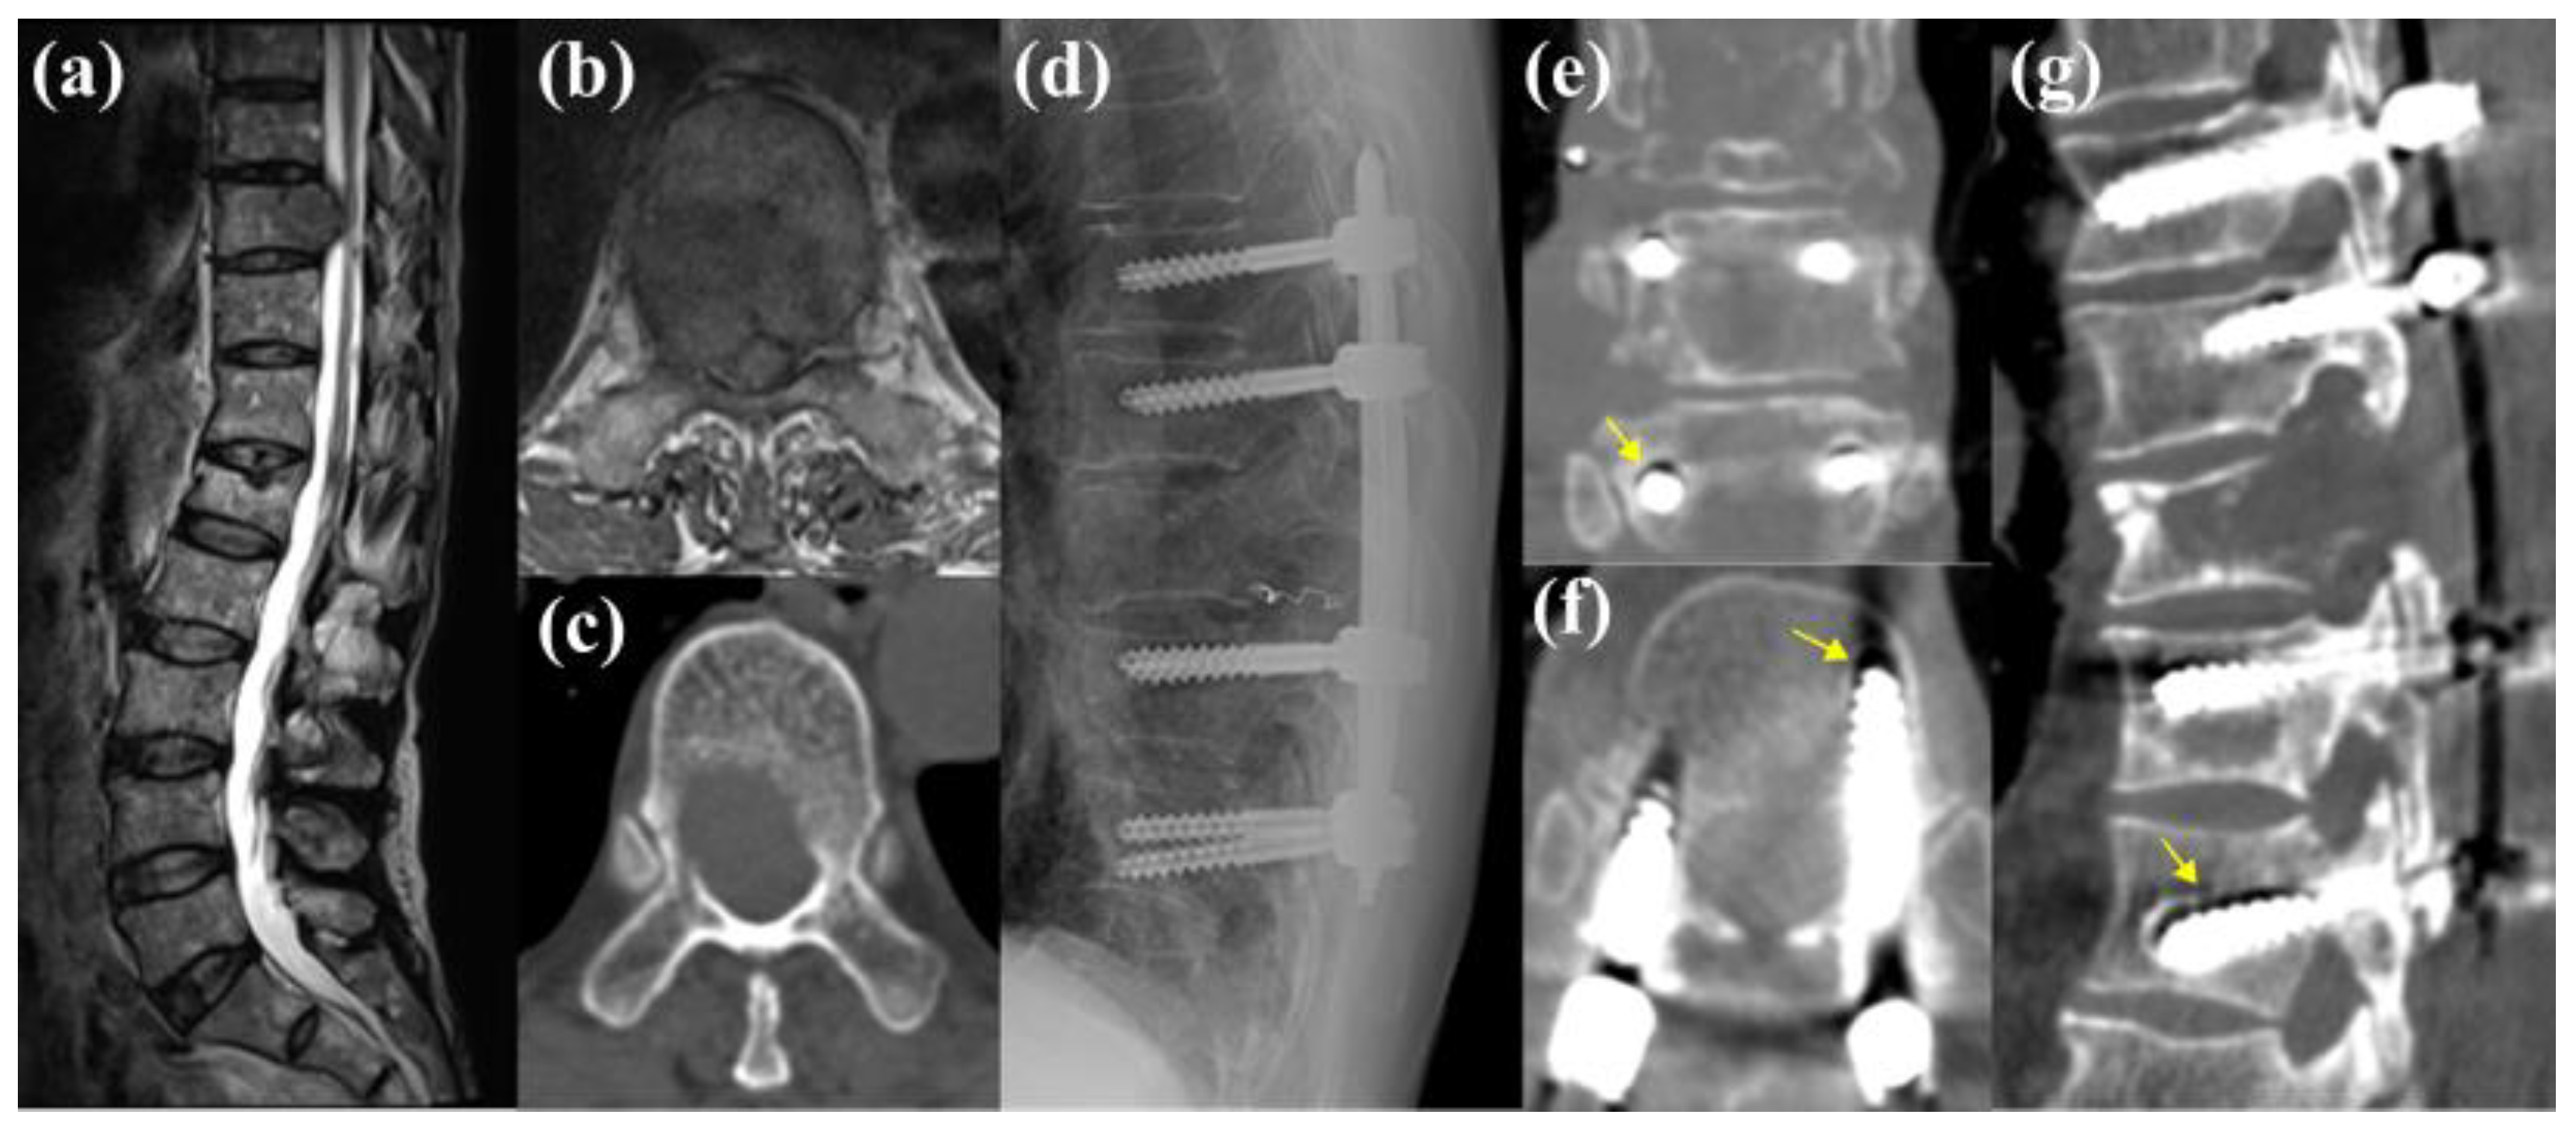

3.5.1. Case 1